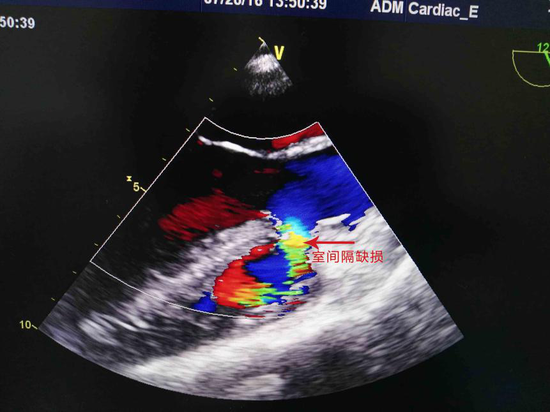

心脏彩超示:室间隔缺损